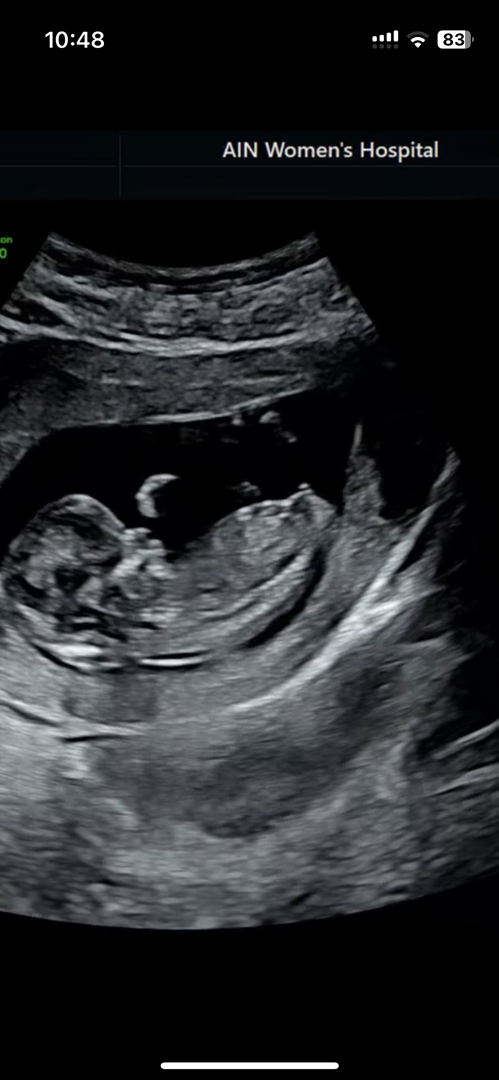

12주 각도법..!

ㅜㅜㅜㅜ다들 아들이라하네요 아들인가욥

생식기가 위로 향한게 아들같아요!